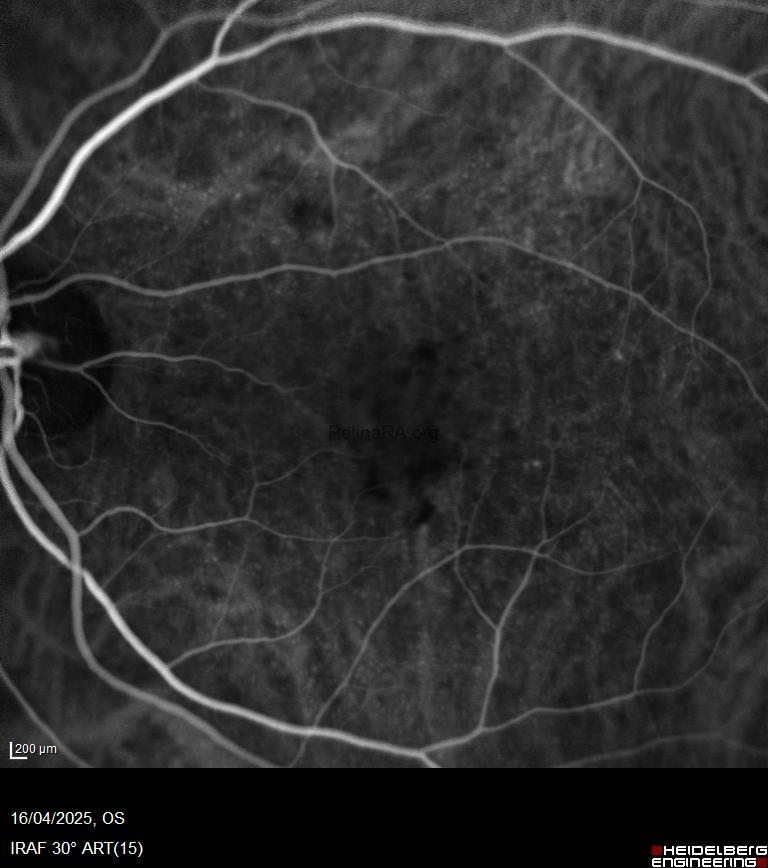

Cuticular drusen, also known as basal laminar drusen, were first described by Gass (1977). They are small, round, yellowish lesions measuring approximately 50–75 μm in diameter. These lesions are typically bilateral and tend to increase in number over time, often clustering and coalescing to form pigment epithelial detachments (PEDs). Cuticular drusen are usually observed in younger adults (40–60 years) and have a strong genetic predisposition, particularly associated with variants in the complement factor H (CFH) gene (Duvvari et al., 2015).

* Fundus Autofluorescence (FAF):

Lesions appear hypoautofluorescent, often bordered by a ring of hyperautofluorescence.